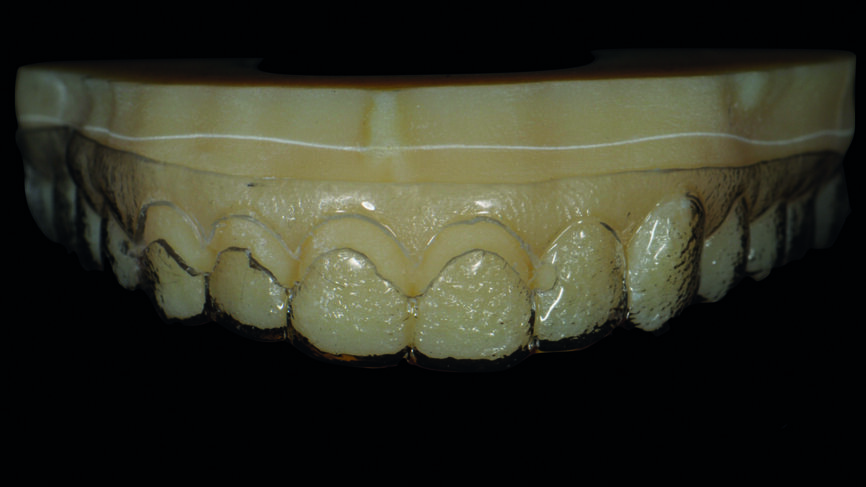

Fig. 4 : Warm-up sur le modèle en plâtre pierre en vue du traitement de restauration des dix dents antérieures.

Fig. 13 : Flux de travail analogique (modèles positifs unitaires réfractaires, fabrication des facettes, ajustements, coloration/glaçage).

Le jeu de facettes en céramique feldspathique a été fabriqué en IPS Style (Ivoclar Vivadent) sur un modèle en plâtre-pierre, tandis qu‘un bloc IPS Empress CAD Multi (Ivoclar Vivadent) a été utilisé pour le jeu numérique (Figs. 13 et 14). Les deux jeux ont été évalués en bouche avec une pâte d‘essai afin de comparer les propriétés optiques des facettes feldspathiques et des facettes réalisées en technique CFAO (Figs. 15a–c).